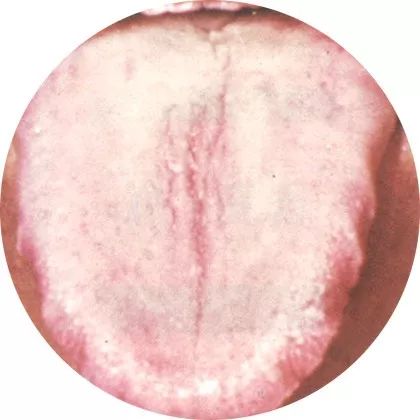

裂纹舌

四、裂纹舌

【舌象特征】舌面上出现各种形状的裂纹、裂沟,沟裂中并无舌苔覆盖。舌上裂纹可多少不等,深浅不一,可见于全舌,亦可见于舌前部或舌尖、舌边等处,裂纹可呈现“人”、“川”、“爻”、“∫”等形状,严重者可如脑回状、卵石状,或如刀割、剪碎一样。

【临床意义】多由邪热炽盛、阴液亏虚、血虚不润所致。

【机理分析】舌红绛而有裂纹,多属热盛伤津。因邪热内盛,阴液大伤,或阴虚液损,使舌体失于濡润,舌面萎缩所致。

舌淡白而有裂纹,多为血虚不润。因血虚不能上荣于舌,精微不能养舌体,可使舌体出现裂纹。

若生来舌面上就有较浅的裂沟、裂纹,裂纹中一般有苔覆盖,且无不适感觉者,称先天性舌裂,应与病理性裂纹加以鉴别。